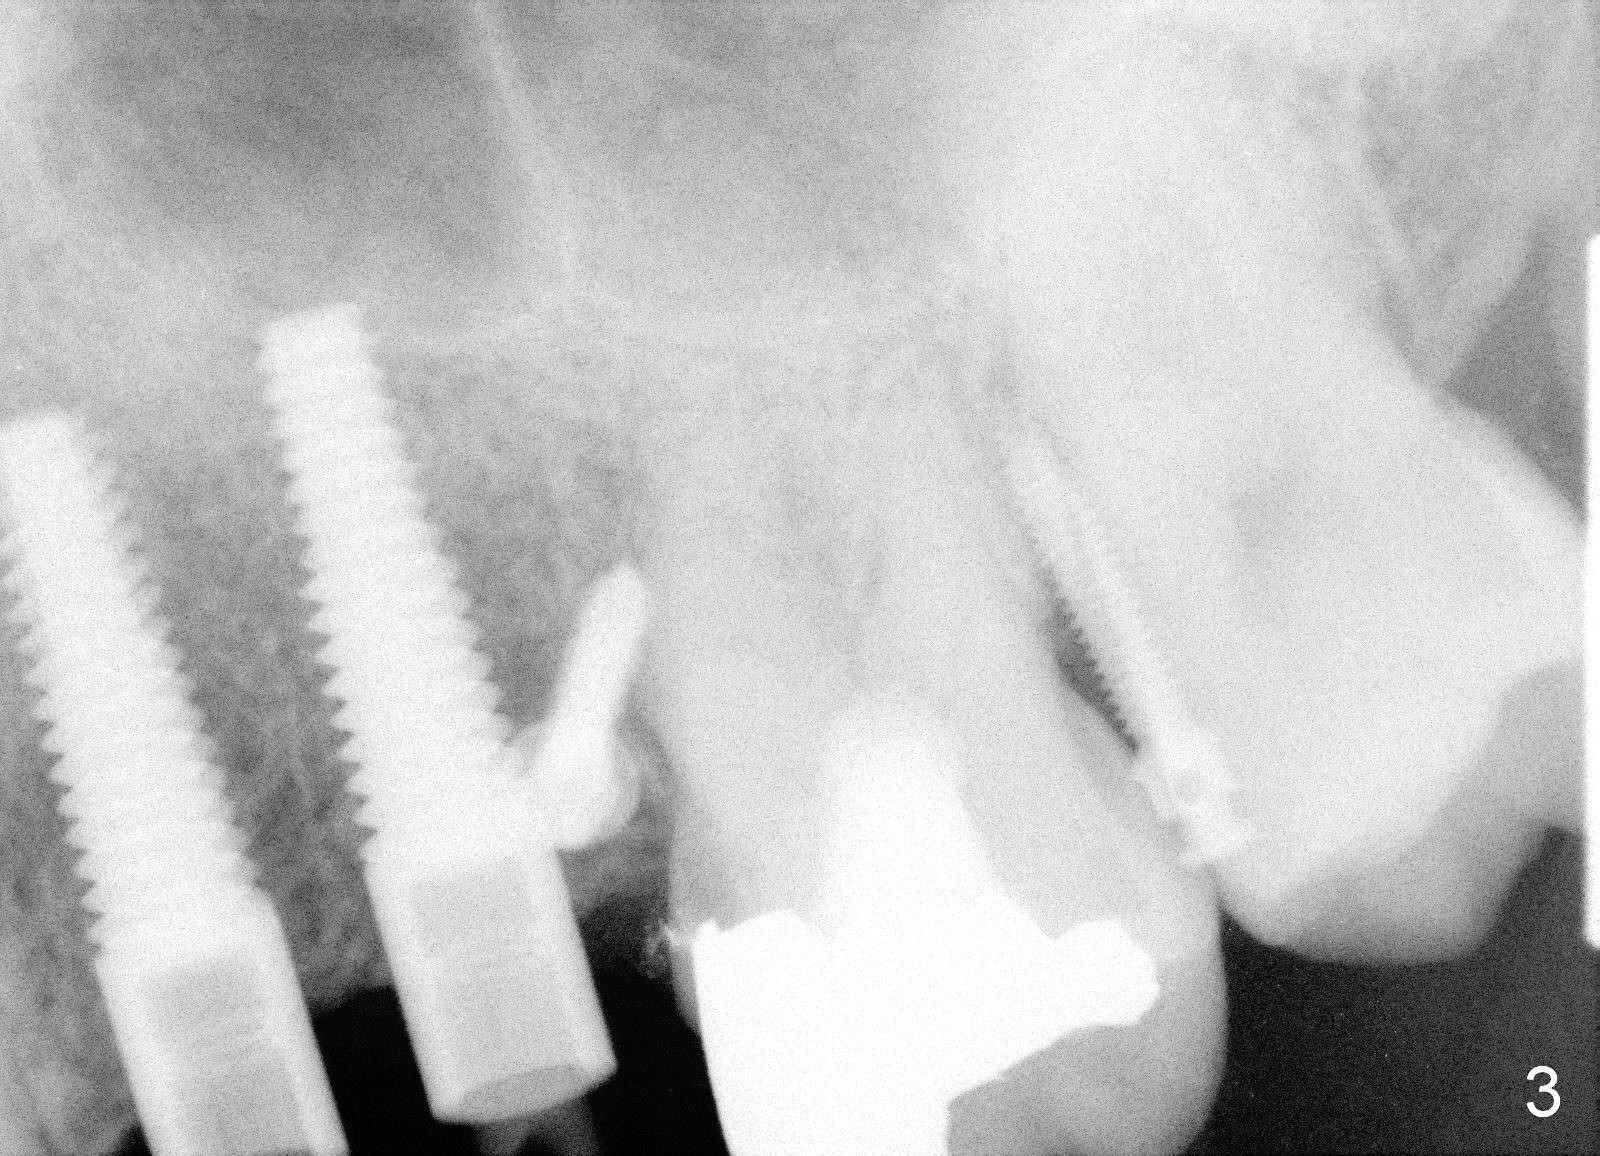

A 51-year-old man returns for #12,13 implant placement 2 years post extraction (Fig.1, 2 mm pilot drills 11 mm deep). Bone expanders are used (Fig.2 E), although the bone density is high. Two of 4x17 mm implant are placed with insertion torque > 60 Ncm (Fig.3). Four months postop, the implants are prepared for provisional as anchorage for limited ortho (Fig.4). When intrusion of #14 is finished, permanent crowns are fabricated for #12 and 13. Fig.5 is taken 1 year 1 months post cementation.